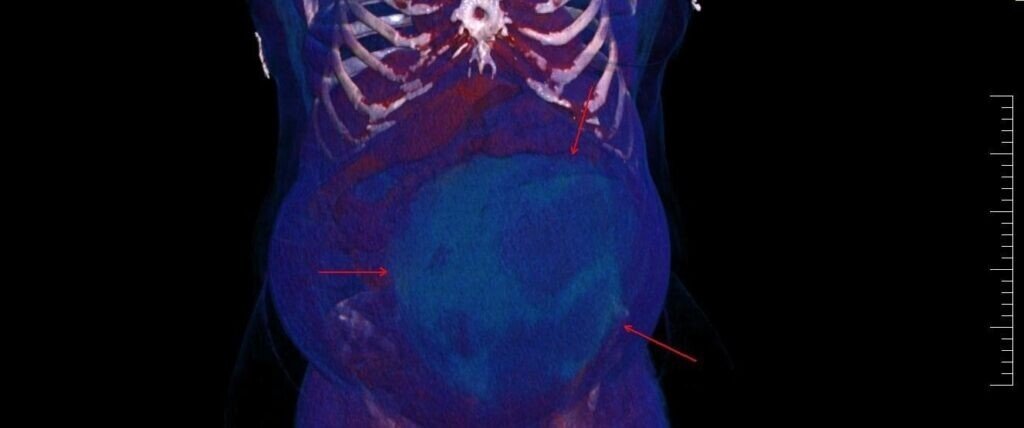

Un chist ovarian voluminos, de 4,5 kg, descoperit la o pacientă, în urma unui consult ginecologic și a unor investigații în cadrul Laboratorului radiologie și imagistică medicală al Spitalului Militar de Urgență ”Dr. Alexandru Augustin” din Sibiu, a fost operat cu succes de colegul nostru, Remus Maxim, medic primar obstetrică-ginecologie.

Existând suspiciunea de neoplasm, medicul din cadrul Compartimentului Ginecologie din Secția Chirurgie Generală a luat decizia de a extrage formațiunea chistică în întregime, operația fiind un succes.